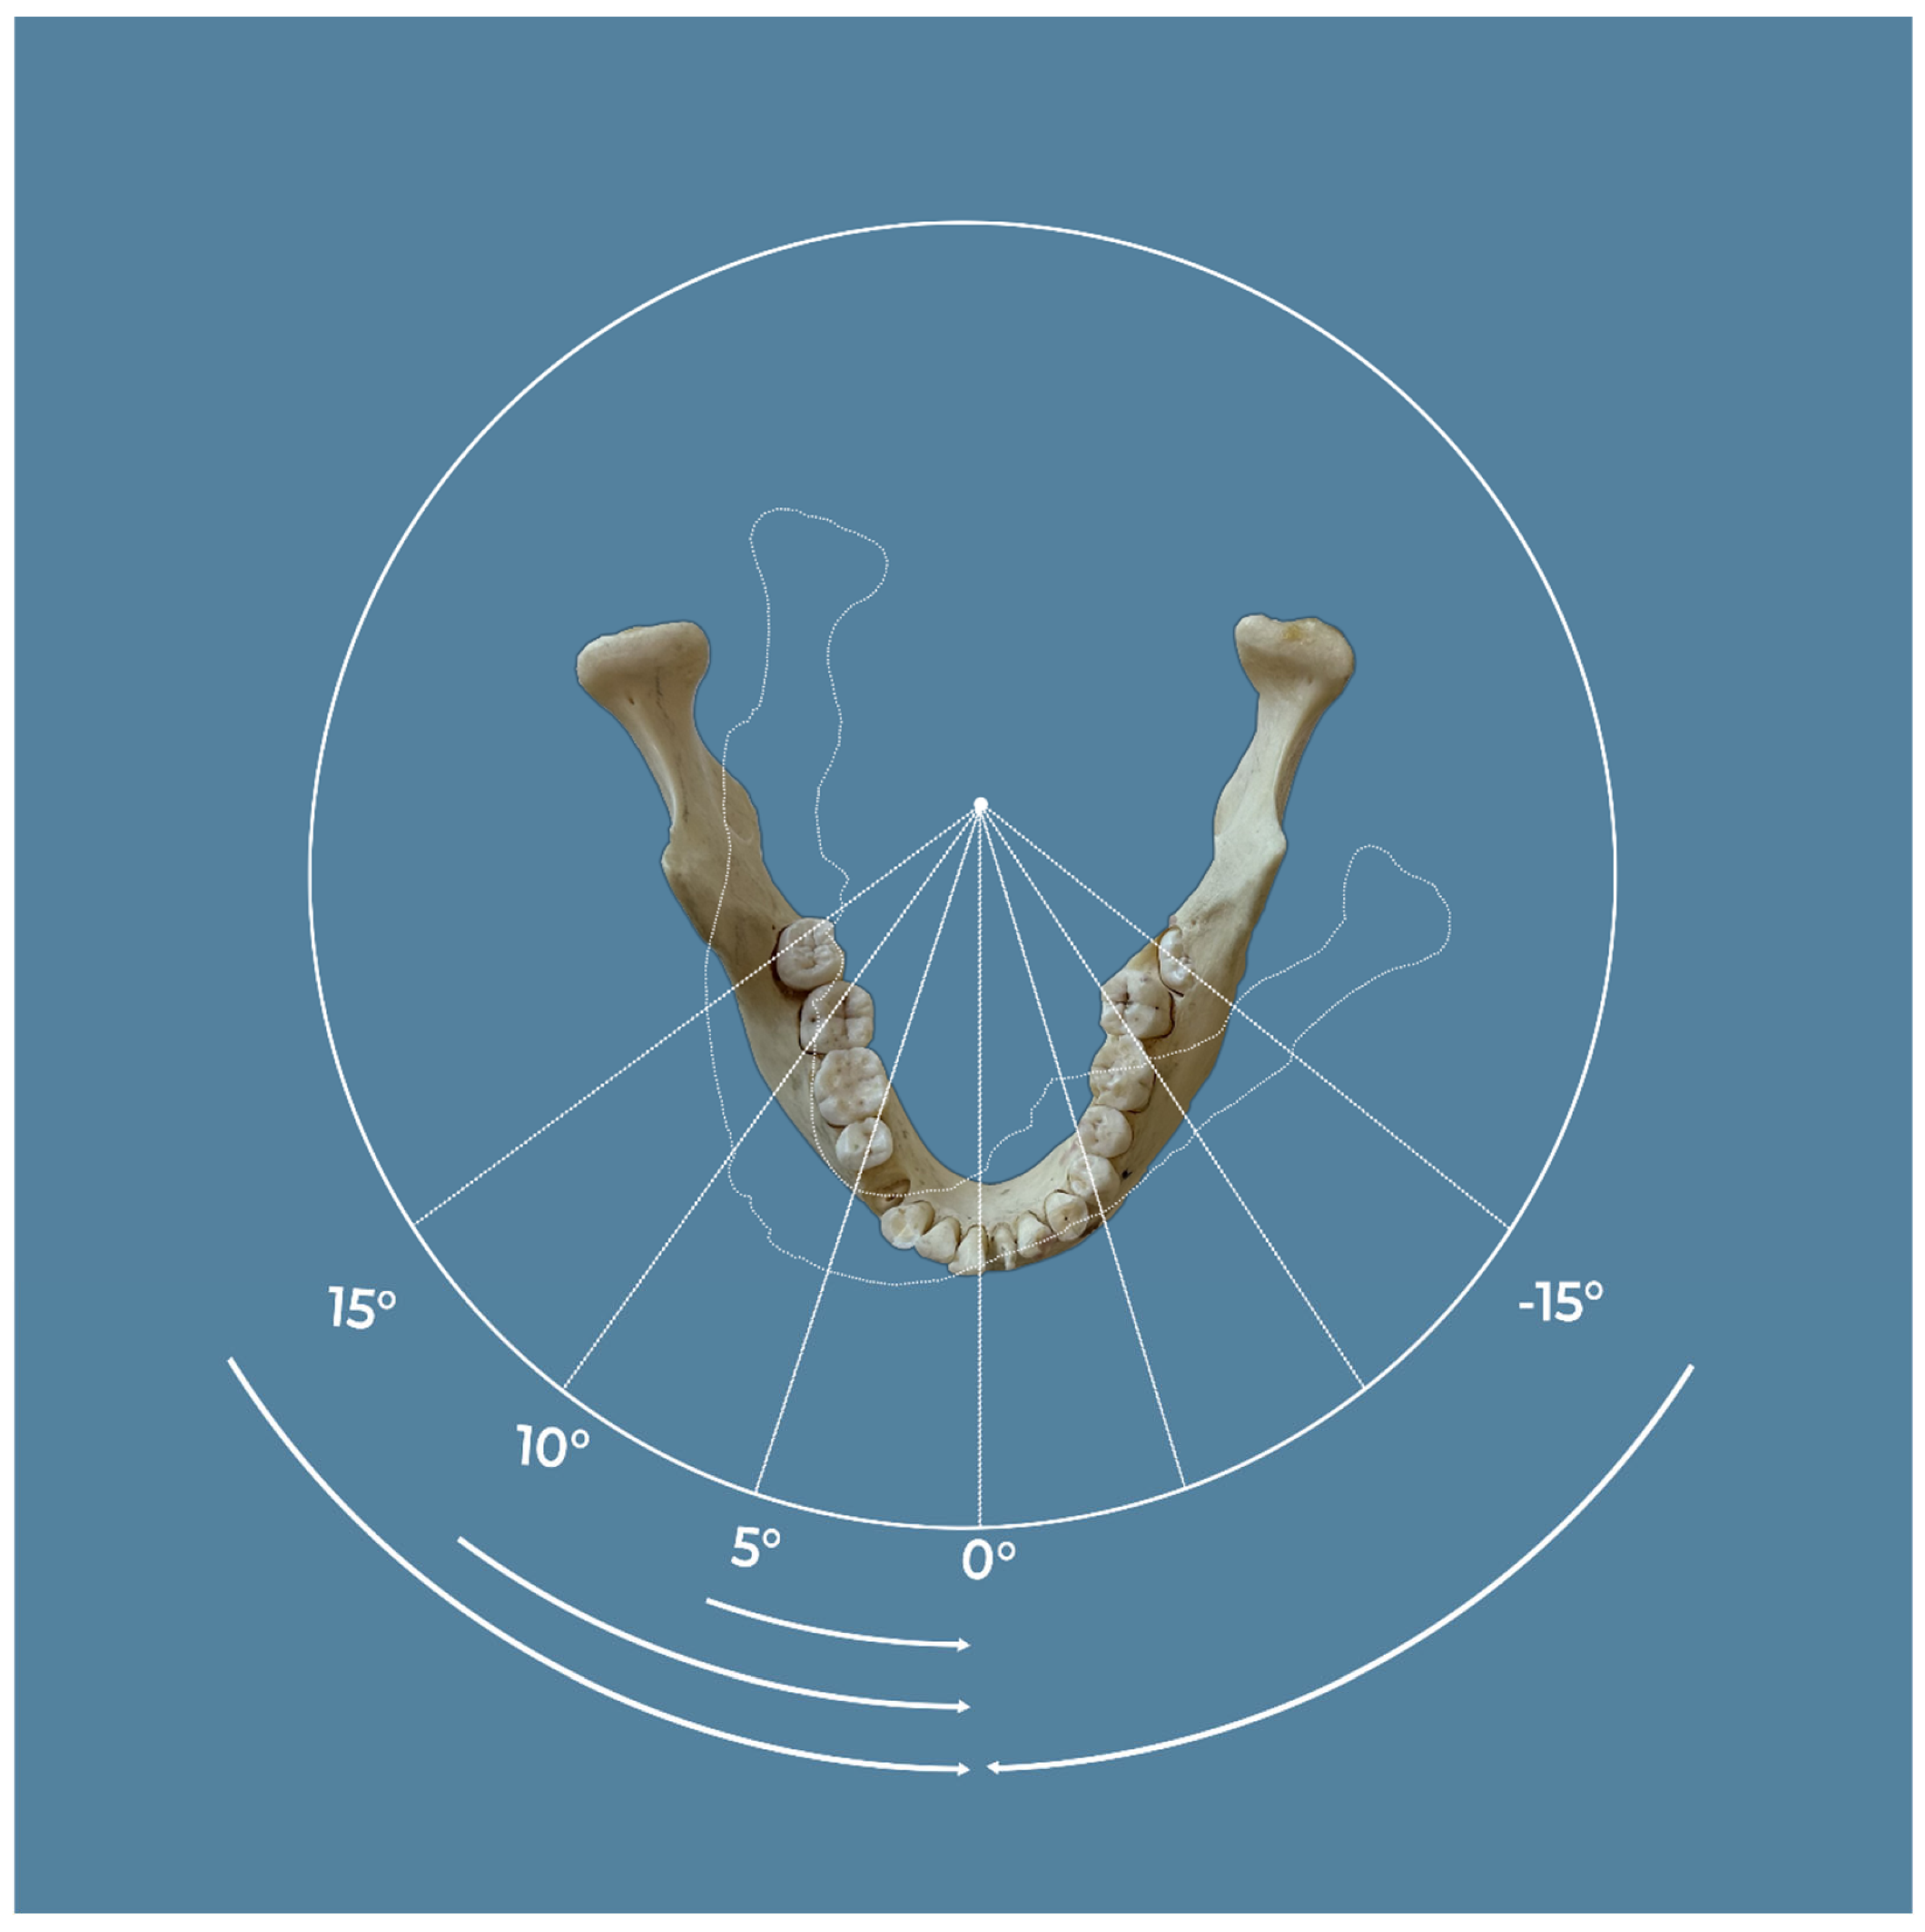

2. Materials and Methods